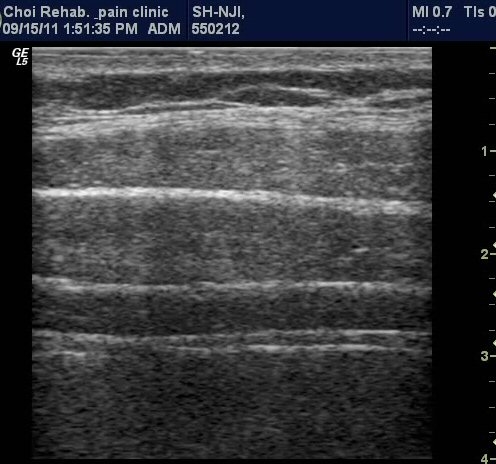

¹è²Å ¿ÜÃø¿¡ ÆÀÃËÀÚ¸¦(ŽÃËÀÚ 1) ´ë°í º¹±ÙÀ» °üÂûÇÔ ¸ð½À, ¼¼ÃþÀÇ º¹±ÙÀÌ °üÂûµÇµµ

°¡Àå ½ÉºÎ¿¡ Ⱦº¹±ÙÀÌ °üÂûµÇ°í ÀÖ´Ù(±×¸² 1). ¼Òº¯À» ÂüÀ¸¼¼¿ä, °ñ¹ÝÀ» ¸Ó¸®ÂÊÀ¸·Î ¿Ã¸®¼¼¿ä,